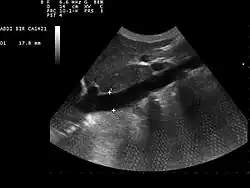

Dans les services de réanimation, la mesure de la variabilité respiratoire du diamètre de la veine cave inférieure par échographie permet d'évaluer la volémie, et donc de prédire la réponse à l'expansion volémique, au cours de la prise en charge d'une instabilité hémodynamique chez un patient sous ventilation mécanique[1],[2].